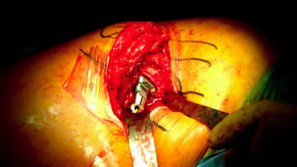

Size 1 rasp could not seat deep enough and would have to use 28 mm head decision made to switch to Apex Modular Stem |

| Only took about 8-10 minutes to prepare for Apex Modular |

Intra-operative x-ray helps check mechanical alignment and modular features allow for last minute fine tuning. Neck length adjusted. Stem fit like a custom implant. 2 prox x 10 mm. |